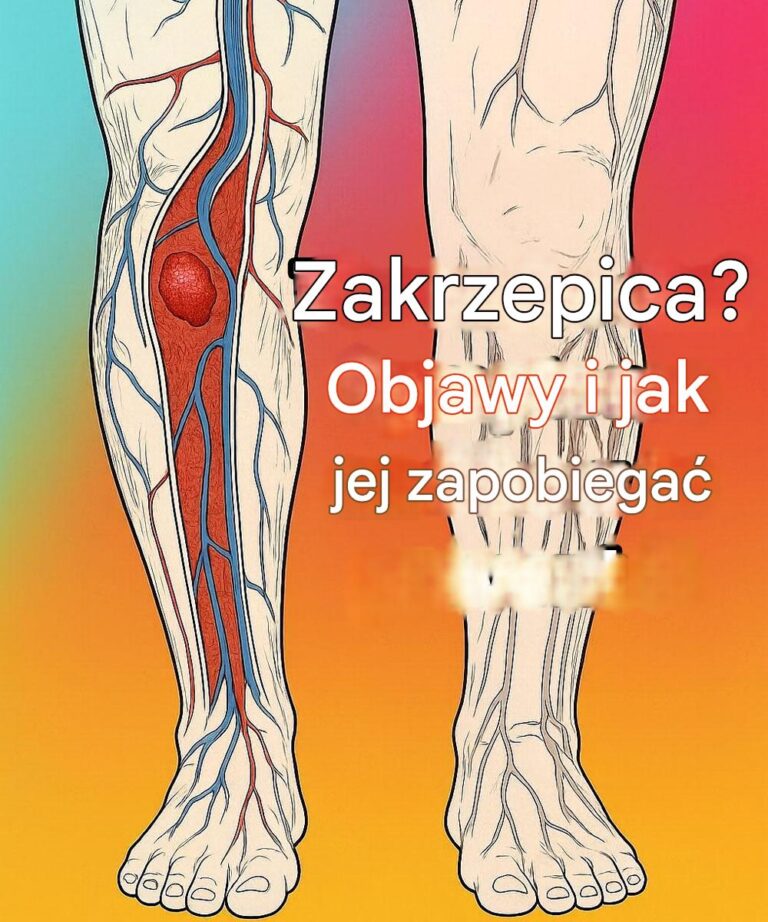

Zakrzepica to stan chorobowy, który występuje, gdy w żyle lub tętnicy tworzy się skrzep krwi, utrudniający prawidłowe krążenie. Ten rodzaj może wystąpić, jeśli nie…